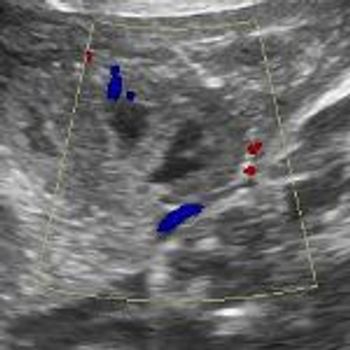

QUIZ: These images show some changes in the placenta of a 34-week pregnancy. Are they anything to worry about?